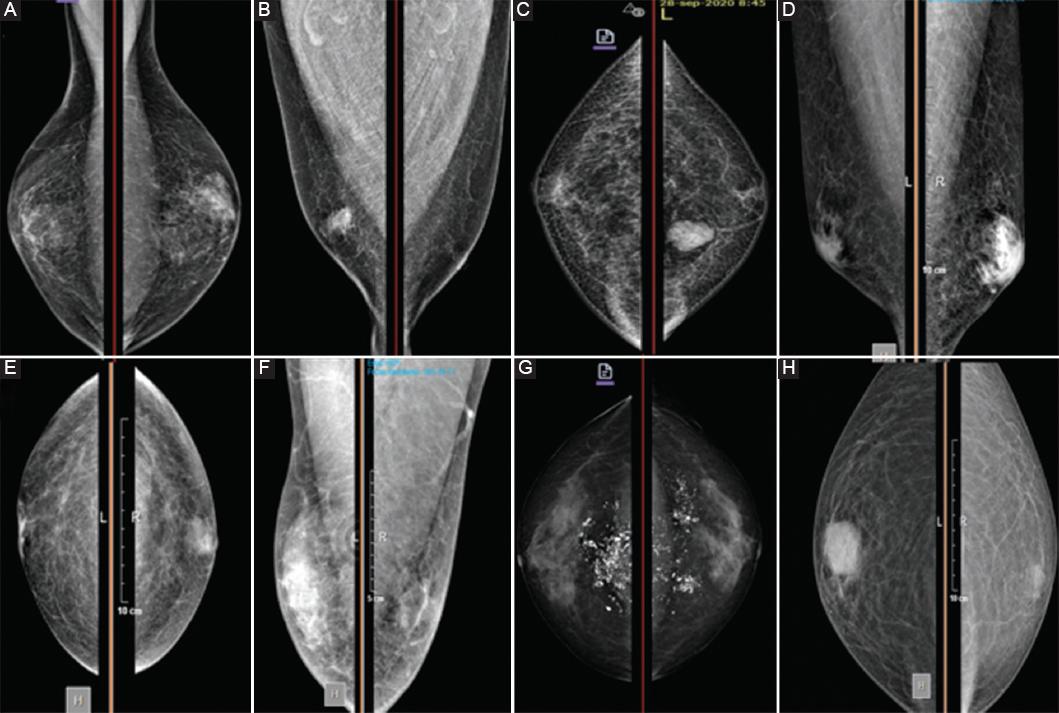

Figura 3 Características mastográficas de lesiones benignas de mama en hombres. A: proyección craneocaudal. Se aprecia un aumento de volumen mamario bilateral con distorsión de la arquitectura. Se realizó biopsia, la cual reportó ginecomastia bilateral. B: proyección craneocaudal. En la mama derecha se observa un nódulo hiperdenso de características irregulares, cuyo reporte histopatológico indicó mastitis. C: proyección craneocaudal. En la mama izquierda se observa un nódulo hiperdenso, con bordes bien delimitados hacia los cuadrantes internos y el tercio posterior. El reporte histopatológico indicó miofibroblastoma. D: proyección mediolateral oblicua. En la mama izquierda se observa un nódulo hiperdenso, mal delimitado, retroareolar, que compromete los cuadrantes superiores e inferiores. El reporte histopatológico indicó hiperplasia ductal usual. E: proyección craneocaudal. En la mama izquierda se aprecia un nódulo mal definido, retroareolar, el cual fue compatible en el reporte histopatológico con fibroadenoma. F: proyección mediolateral oblicua. En la mama derecha se observa una zona hiperdensa que abarca los cuadrantes superiores e inferiores en el tercio medio, de forma irregular, en la cual se reportó lesión papilar. G: proyección craneocaudal. En la mama izquierda se observa una zona de sistematización, con distorsión de la arquitectura que abarca los cuadrantes externos e internos. En ambas mamas se aprecian múltiples calcificaciones de aspecto benigno. El reporte histopatológico indicó ectasia ductal. H: proyección craneocaudal. En la mama derecha se observa un nódulo hiperdenso, con bordes bien definidos, retroareolar, que en la biopsia por aguja fina fue drenado y el estudio histopatológico indicó tuberculosis.